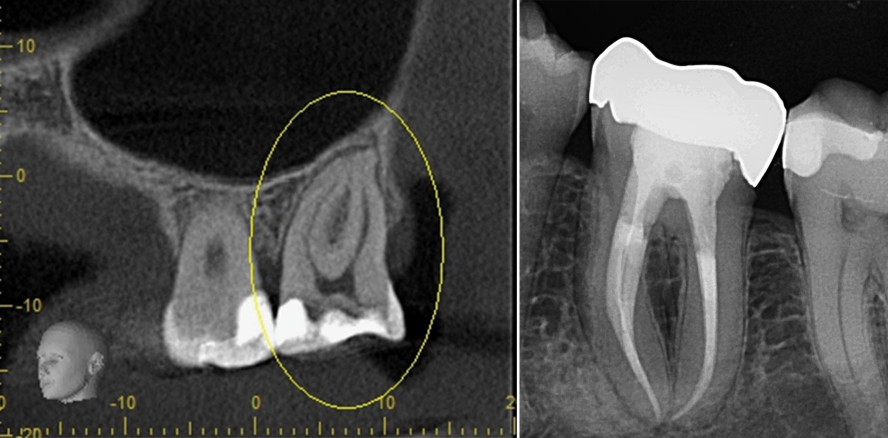

Die Präparation des Zahnes erfolgt entsprechend der anatomischen Lage der Wurzelkanaleingänge – bewährte Schemata dafür liegen vor. Die Möglichkeit der dreidimensionalen Dia­gnostik mittels DVT bietet einen zusätzlichen Schutz, um wertvolle Zahnhartsubstanz zu erhalten und trotzdem einen geradlinigen Zugang zu den Kanalorifizien zu ermöglichen.

Im Rahmen der Diagnostik und unter Einbeziehung sinnvoller Technik muss eine Vorstellung davon entwickelt werden, WAS mechanisch bearbeitet werden soll. Daraus kann sich die Einsicht ergeben, WIE es bearbeitet werden kann. Zentrale Kriterien für die Auswahl der Wurzelkanalinstrumente sind die Effizienz und die Sicherheit eines Feilensystems unter den gegebenen Umständen. Daneben sind die Kosten, die Einflüsse auf die Zahnsubstanz und die Voraussetzungen für eine optimale Wurzelkanalfüllung Faktoren für die Beantwortung der Frage, ob ein System geeignet ist, eine zeitgemäße endodontische Behandlung zu ermög­lichen.